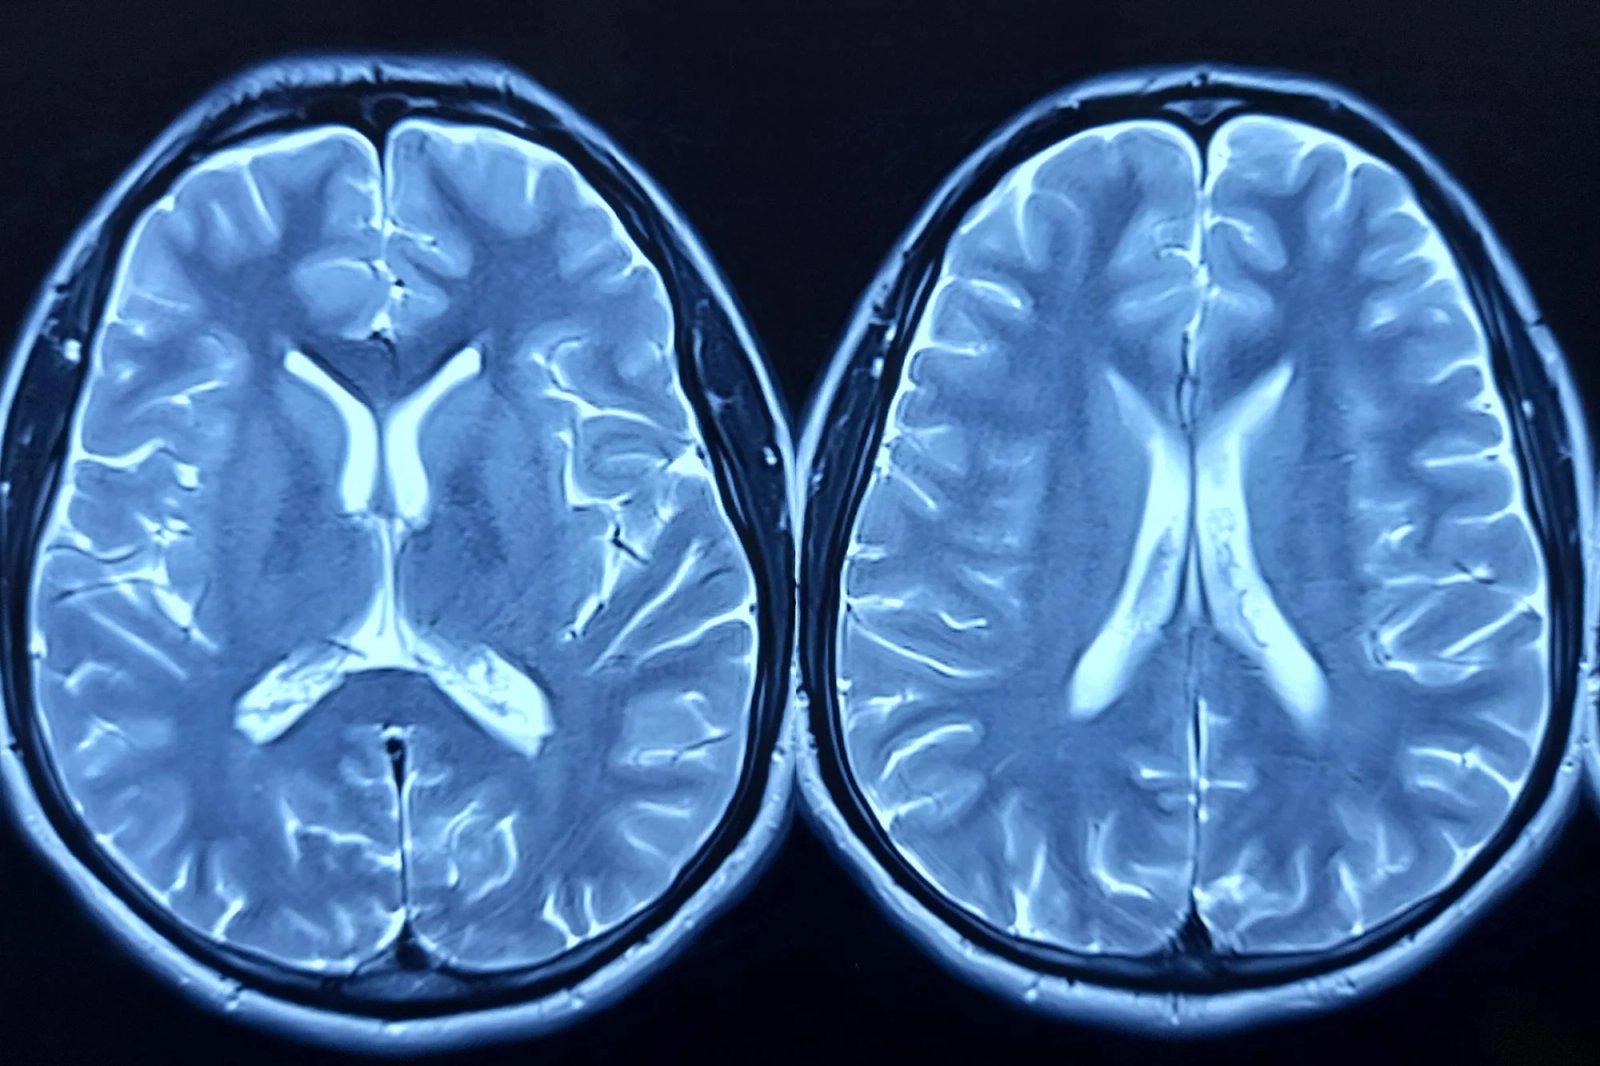

أظهرت نظرة نادرة على نشاط الدماغ لمريض يعاني من السمنة وفقدان السيطرة على الأكل وكان يتناول عقار تيرزيباتيد (الذي يباع باسم مونجارو وزيباوند) أن الدواء يمكن أن يقلل الإشارات في “مركز المكافأة” في الدماغ، والذي يرتبط بضوضاء الطعام، على الرغم من أن هذا التأثير كان مؤقتًا فقط.

تظهر الأبحاث أن سلوكيات الأكل، بما في ذلك نوبات الشراهة، تتشكل من خلال شبكات الدماغ التي تنطوي على منطقة ما تحت المهاد ومركز المكافأة المعروف باسم النواة المتكئة (NAc). يلعب NAc دورًا رئيسيًا في نظام تحفيز الدماغ ويؤثر على الاختيارات المتعلقة بتنظيم المتعة والاندفاعات. دراسات سابقة لقد وجد أنه في الأشخاص الذين يعانون من السمنة واضطراب الأكل القهري، والذي يحدث غالبًا معًا، تتعطل الإشارة داخل NAc والدوائر المحيطة بها.

في هذه التجربة الحالية التي تضم أربعة مشاركين، يتم زرع أقطاب تخطيط كهربية الدماغ (iEEG) في دماغ شخص يعاني من السمنة ويعاني من فقدان السيطرة على الأكل، على غرار الأجهزة المستخدمة لدراسة وعلاج الصرع المقاوم للأدوية ومرض باركنسون. في هذه الحالة، يسجل الجهاز النشاط الكهربائي في NAc حيث يواجه المشاركون الأطعمة التي تؤدي عادة إلى نوبات الشراهة عند تناول الطعام.